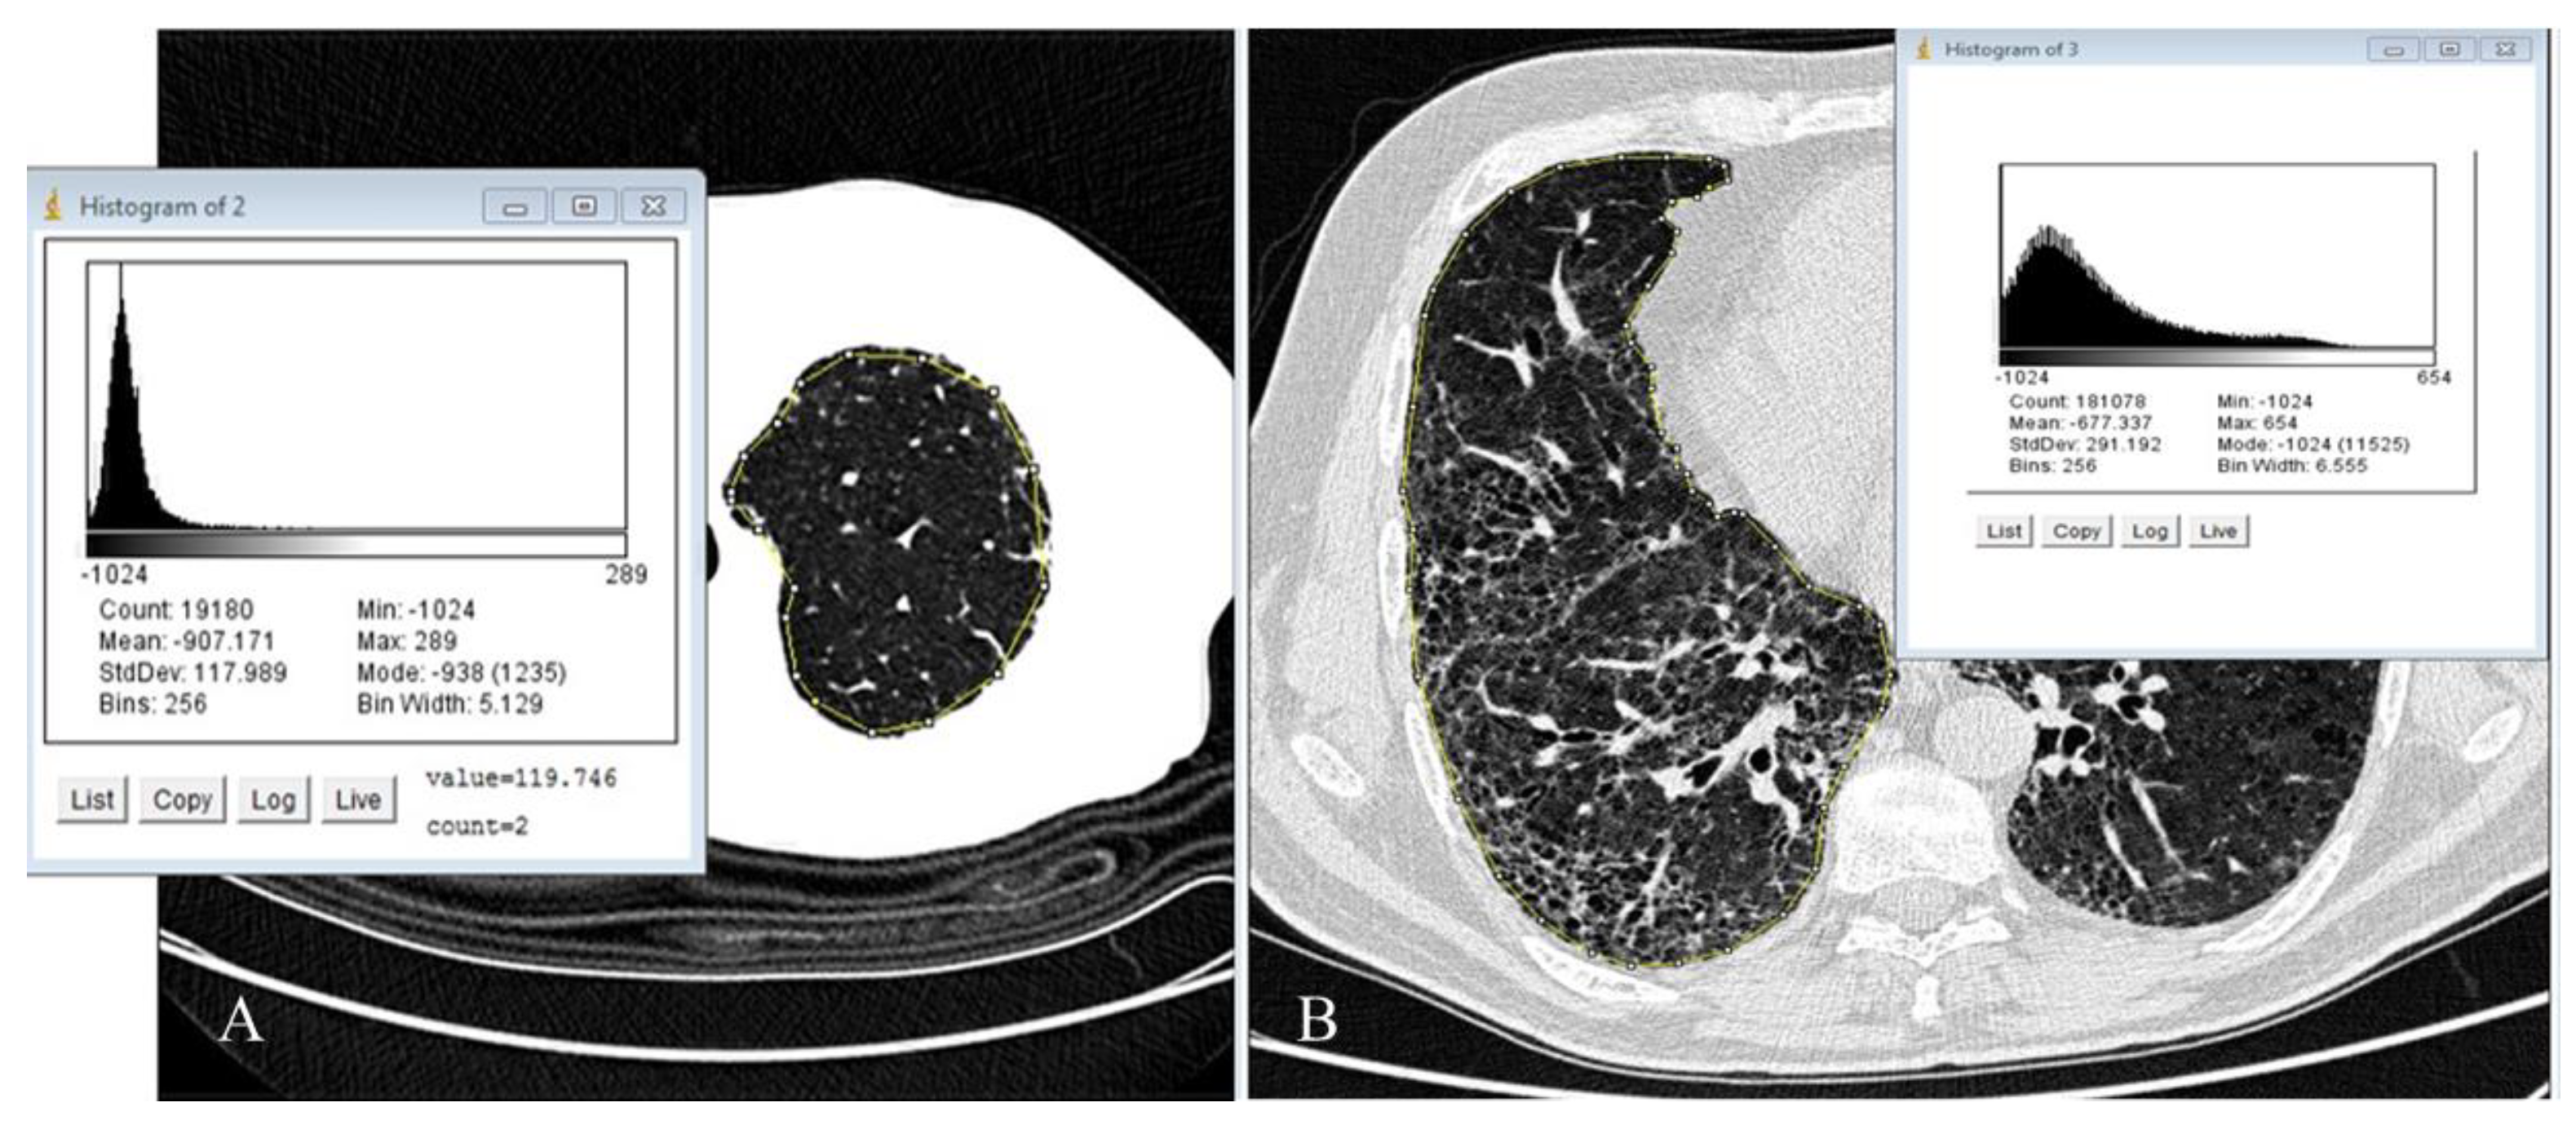

- Rea, G.; De Martino, M.; Capaccio, A.; Dolce, P.; Valente, T.; Castaldo, S. Comparative analysis of density histograms and visual scores in incremental and volumetric high-resolution computed tomography of the chest in idiopathic pulmonary fibrosis patients. Radiol. Med. 2021, 126, 599–607. [Google Scholar] [CrossRef]

- Bocchino, M.; Bruzzese, D.; D′Alto, M.; Argiento, P.; Borgia, A.; Capaccio, A.; Romeo, E.; Russo, B.; Sanduzzi, A.; Valente, T.; et al. Performance of a new quantitative computed tomography index for interstitial lung disease assessment in systemic sclerosis. Sci. Rep. 2019, 9, 9468. [Google Scholar] [CrossRef]

- Ariani, A.; Carotti, M.; Gutierrez, M.; Bichisecchi, E.; Grassi, W.; Giuseppetti, G.M.; Salaffi, F. Utility of an open-source DICOM viewer software (OsiriX) to assess pulmonary fibrosis in systemic sclerosis: Preliminary results. Rheumatol. Int. 2014, 34, 511–516. [Google Scholar] [CrossRef] [PubMed]